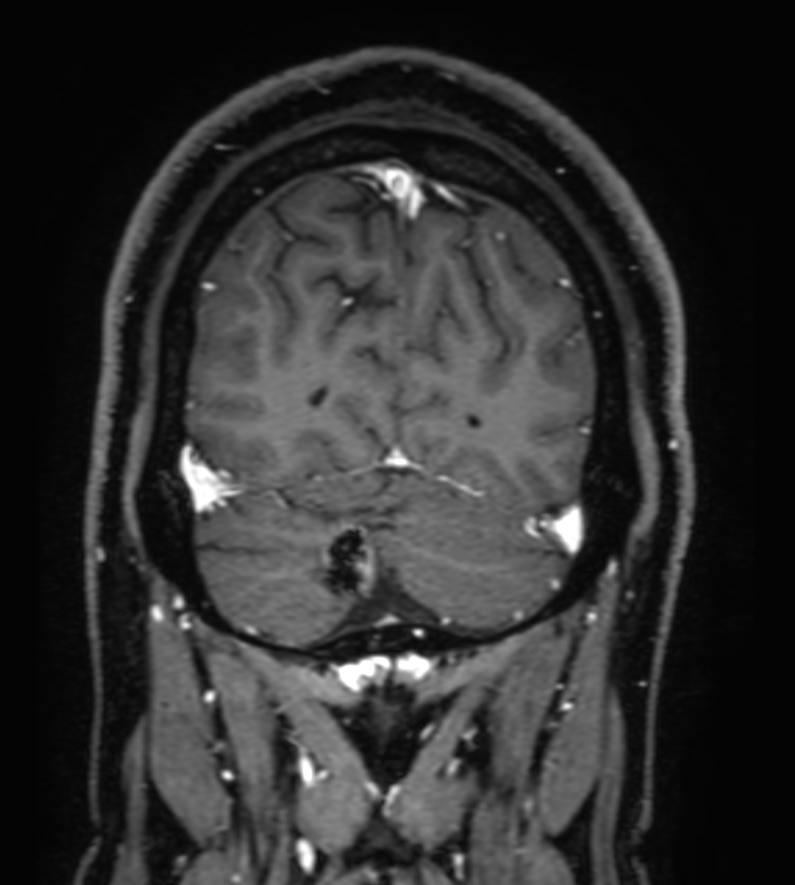

Patient with a lesion in the cerebellum. The ExamCard includes Compressed SENSE to accelerate the entire exam and techniques for motion reduced imaging (MultiVane XD), 3D imaging to acquire high resolution data in multiple directions, 3D susceptibility weighted imaging (SWIp), angiography sequences (Time-of-Flight and Contrast-Enhanced MRA with both arterial and venous phases), DTI with MultiBand SENSE to acquire a high number of diffusion directions in a short scan time and EPIC Brain to bring down any residual distortion.

3D T1w FFE FatSat post-gado Compressed SENSE